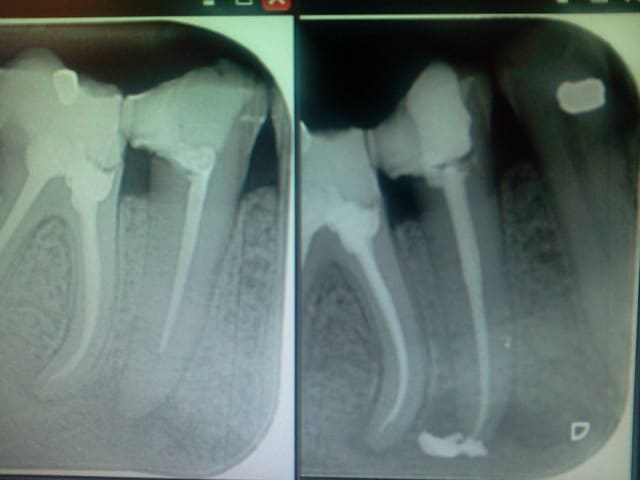

Cas : Patiente 45 ans, dent 37, gros réflexe nauséeux, ouverture buccale limitée à 2.5 travers de doigts, impossible de passer capteur rvg + digue pour vérifier la longueur de travail, pas de localisateur d'apex.

A l'essayage des cônes, le MV bloquais à 22 (longueur que j'avais mesurée sur la radio pré op avant de poser la digue).

Obturation au thermo-compacteur... et là... le drame... Mon cône à filé bien plus loin que prévu...

Le canal ML n'est pas très beau mais il a un apex commun avec l'autre !

Moralité : j'ai acheté un localisateur d'apex dans l'heure qui a suivi ! et dorénavant, en cas de doute, je démonterai la digue pour une rx cône en place avant de la remettre pour obturer !